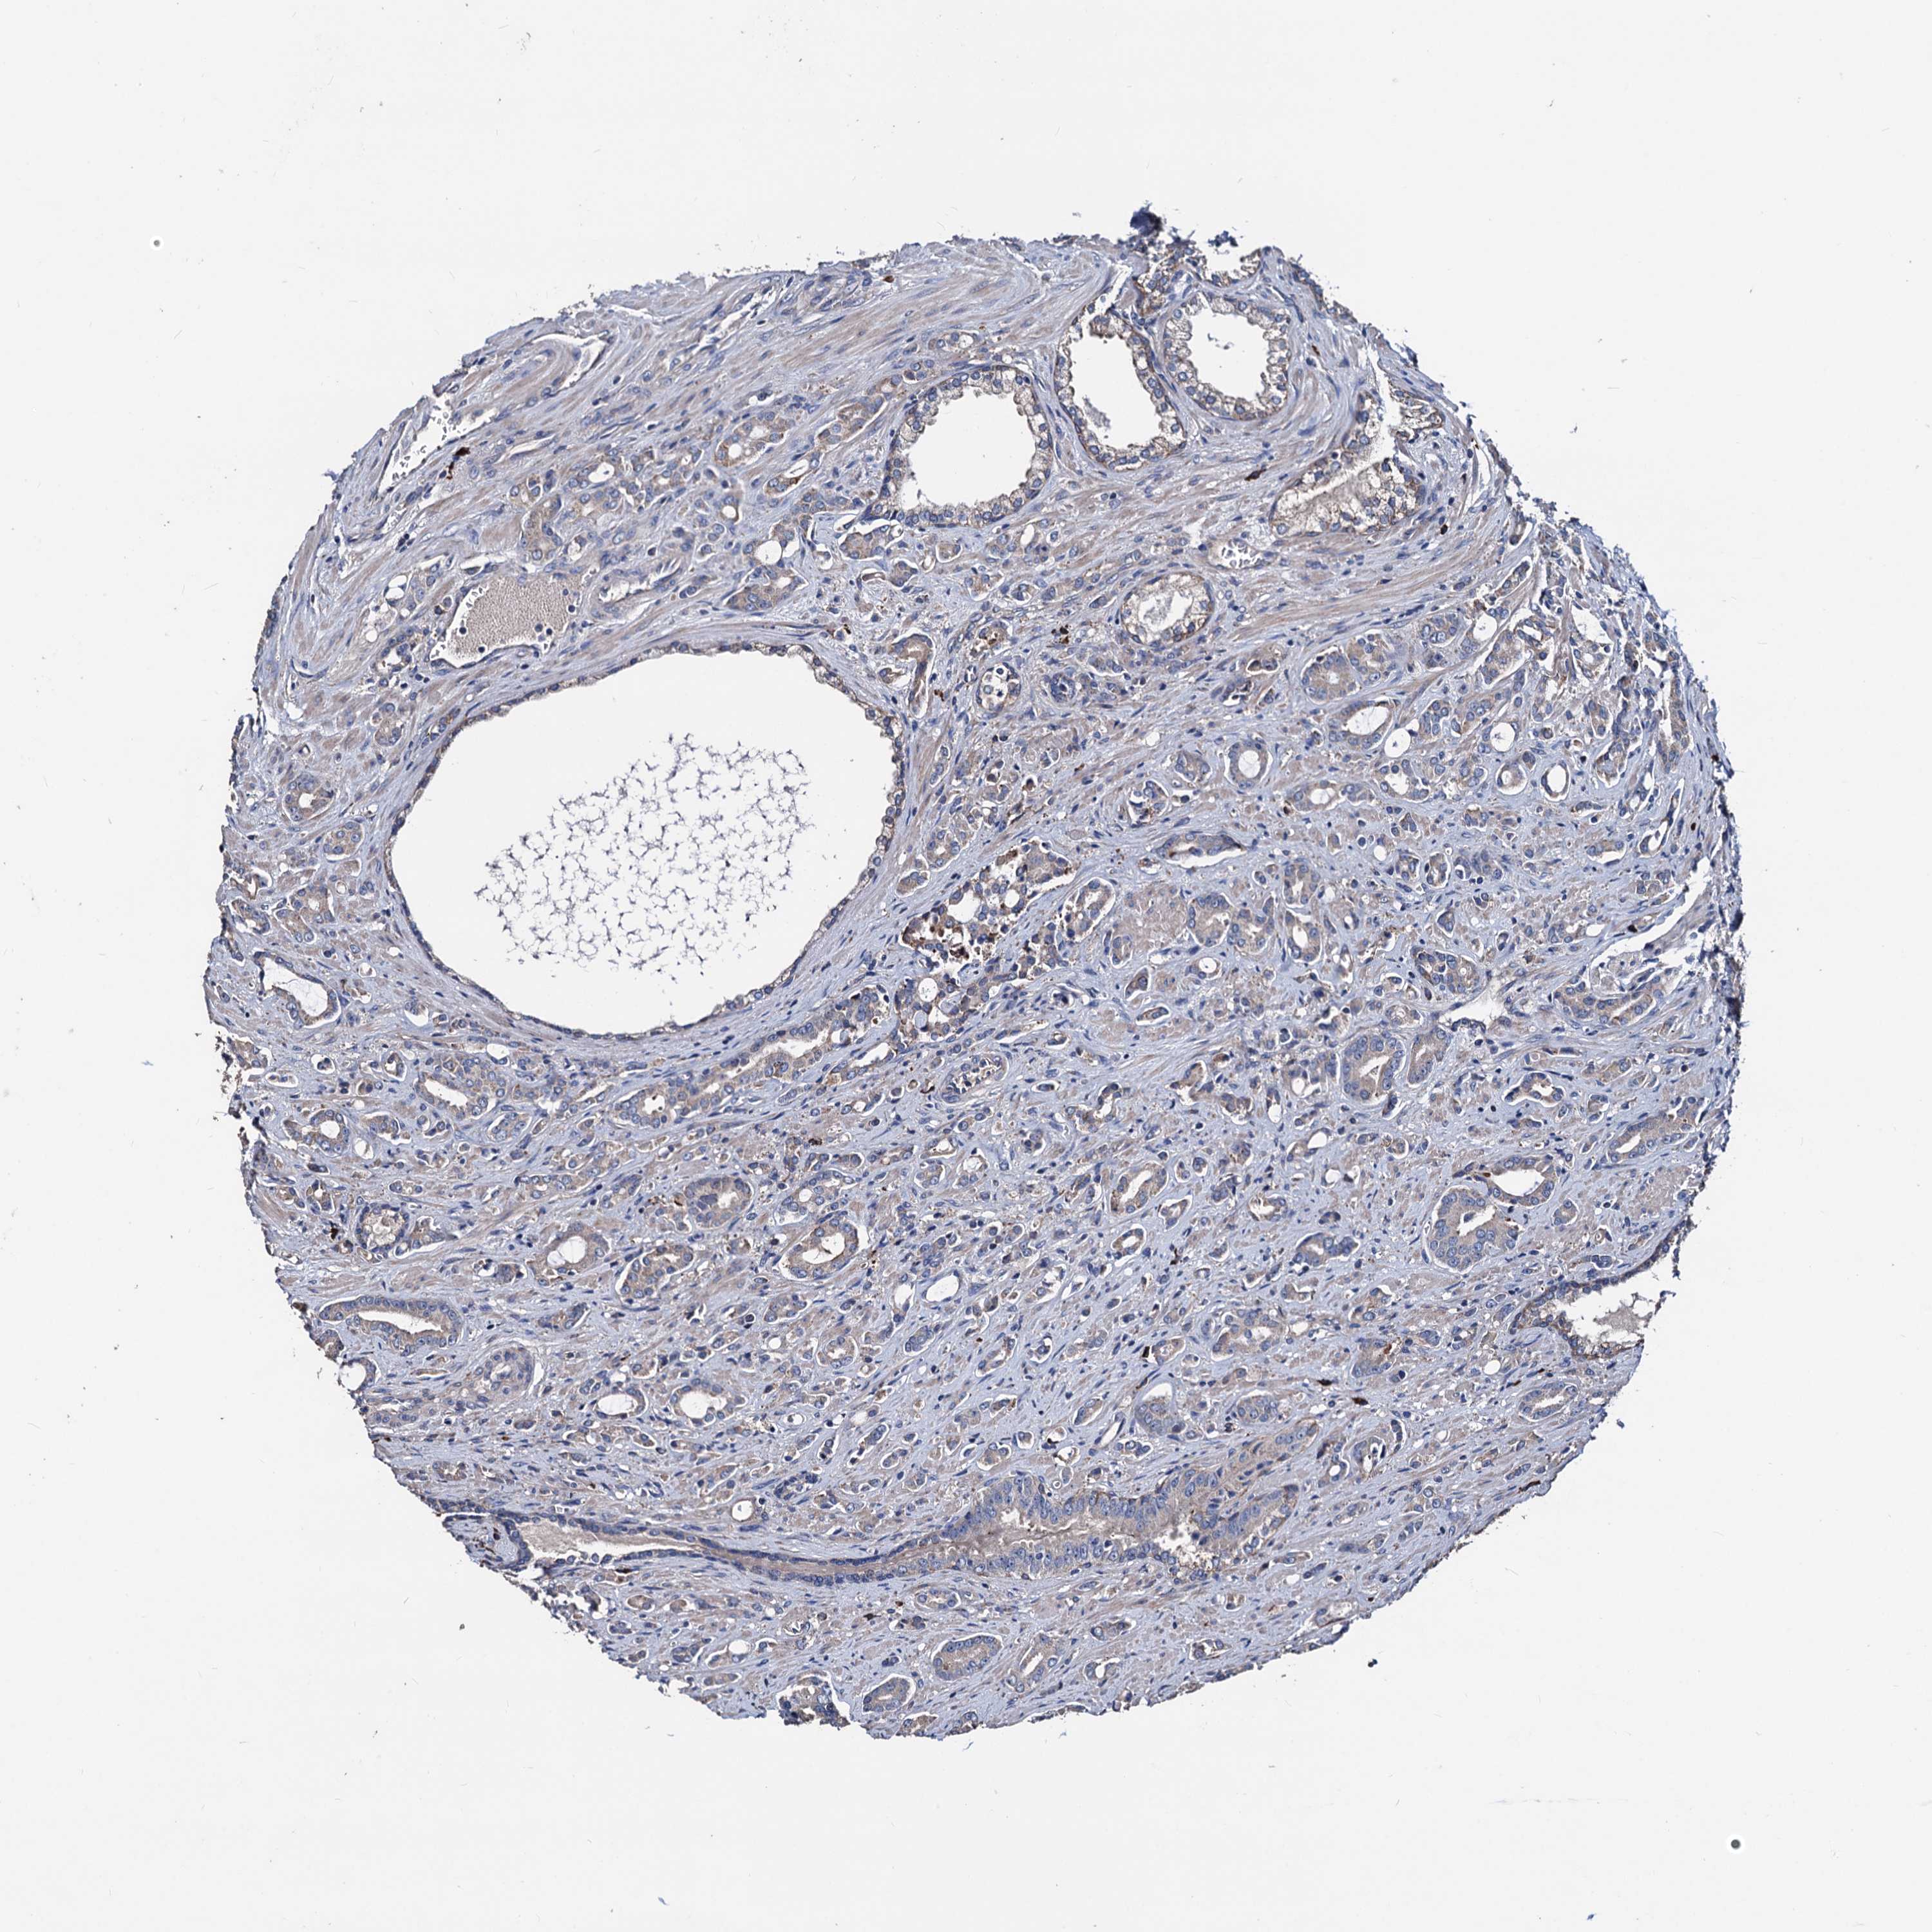

PROSTATE CANCER - Protein expressioni

A mouse-over function shows sample information and annotation data. Click on an image to view it in a full screen mode. Samples can be filtered based on level of antibody staining by selecting one or several of the following categories: high, medium, low and not detected. The assay and annotation is described here.

Note that samples used for immunohistochemistry by the Human Protein Atlas do not correspond to samples in the TCGA dataset.

Antibody stainingi

Antibody staining in the annotated cell types in the current human tissue is reported as not detected, low, medium, or high, based on conventional immunohistochemistry profiling in selected tissues. This score is based on the combination of the staining intensity and fraction of stained cells.

Each image is clickable and will lead to virtual microscopy that enables deeper exploration of all samples and also displays staining intensity scores, fraction scores and subcellular localization as well as patient and tissue information for each sample.

Antibody HPA039089

Staining

High

Medium

Low

Not detected

Intensity

Strong

Moderate

Weak

Negative

Quantity

>75%

75%-25%

<25%

None

Location

Nuclear

Cytoplasmic/membranous

Cytoplasmic/membranous,nuclear

Adenocarcinoma, NOS

Adenocarcinoma, High grade

Adenocarcinoma, Low grade